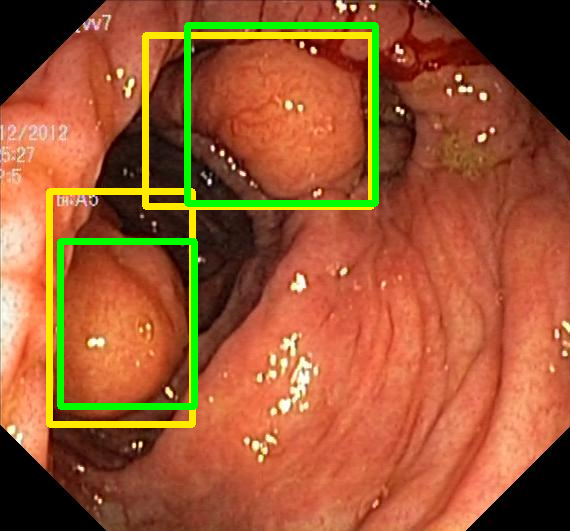

We evaluate the resulting object detection models using the test data, which is pre-processed in the same manner as the validation data, with AP@[.5:.95] (AP for conciseness), AP@.5 (AP50), and AP@.75 (AP75) computed for predicted bounded boxes with a confidence score \geq0.05. For all metrics, a higher value indicates better performance. The results are presented in Table VI, and some examples for predicted bounding boxes with a confidence score \geq0.5 are shown in Fig. 1.

Figure 1: Targets (yellow bounding boxes) and predictions (green bounding boxes) for two randomly selected instances of the Kvasir-SEG test set. For conciseness, we denote ResNet50s with RN, ViT-Bs with VT, Hyperkvasir-unlabelled with HK, ImageNet-1k with IN, MoCo v3 with MC, Barlow Twins with BT, MAE with MA, supervised pretraining with SL, and no pretraining with NA-NA.